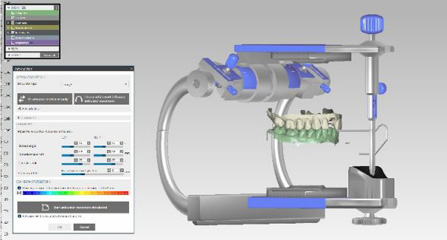

麦芽口腔着眼于全链条的数字化诊疗解决方案,与德国Kavo、瑞典Nobel、韩国奥齿泰、中国康泰健等国际知名齿科品牌合作,建立“深圳数字化口腔联盟”,应用全数字化口腔模式,从CBCT数据提取、AI口扫取模、AI智能口腔体检、数字化分析模拟与方案设计、3D打印、CAD/CAM椅旁加工以及手术模拟导航等,全流程打通数字化口腔精确诊疗的各个环节,实现麦芽数字化口腔诊疗体系新升级。

一体化CAD/CAM义齿加工 即刻有牙